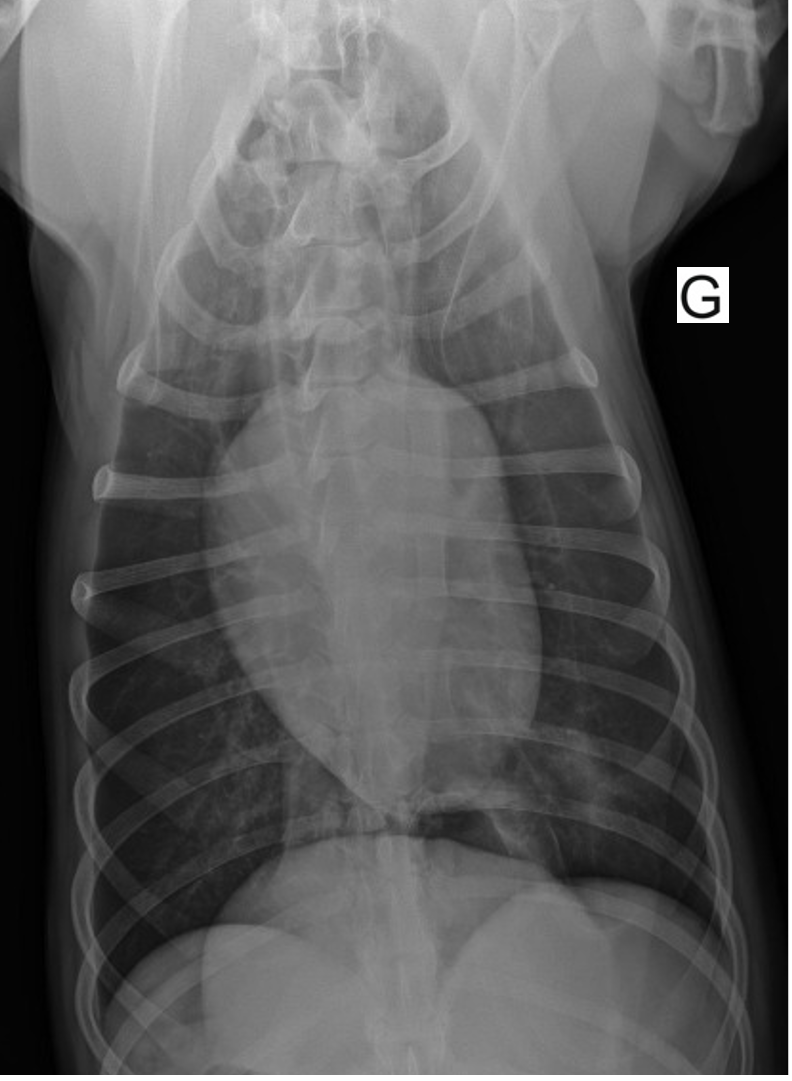

Il est décidé de réaliser une approche conservatrice. Un rendez-vous de contrôle est fixé 15 jours après l’accident. La chienne est en bon état général et sa fréquence respiratoire est dans les normes de l’espèce. Des radiographies thoraciques sont réalisées et montrent une normalisation des images avec disparition des pseudokystes (figures 7 et 8).

Figure 8 : Radiographie du thorax lors du contrôle, vue ventro-dorsale.